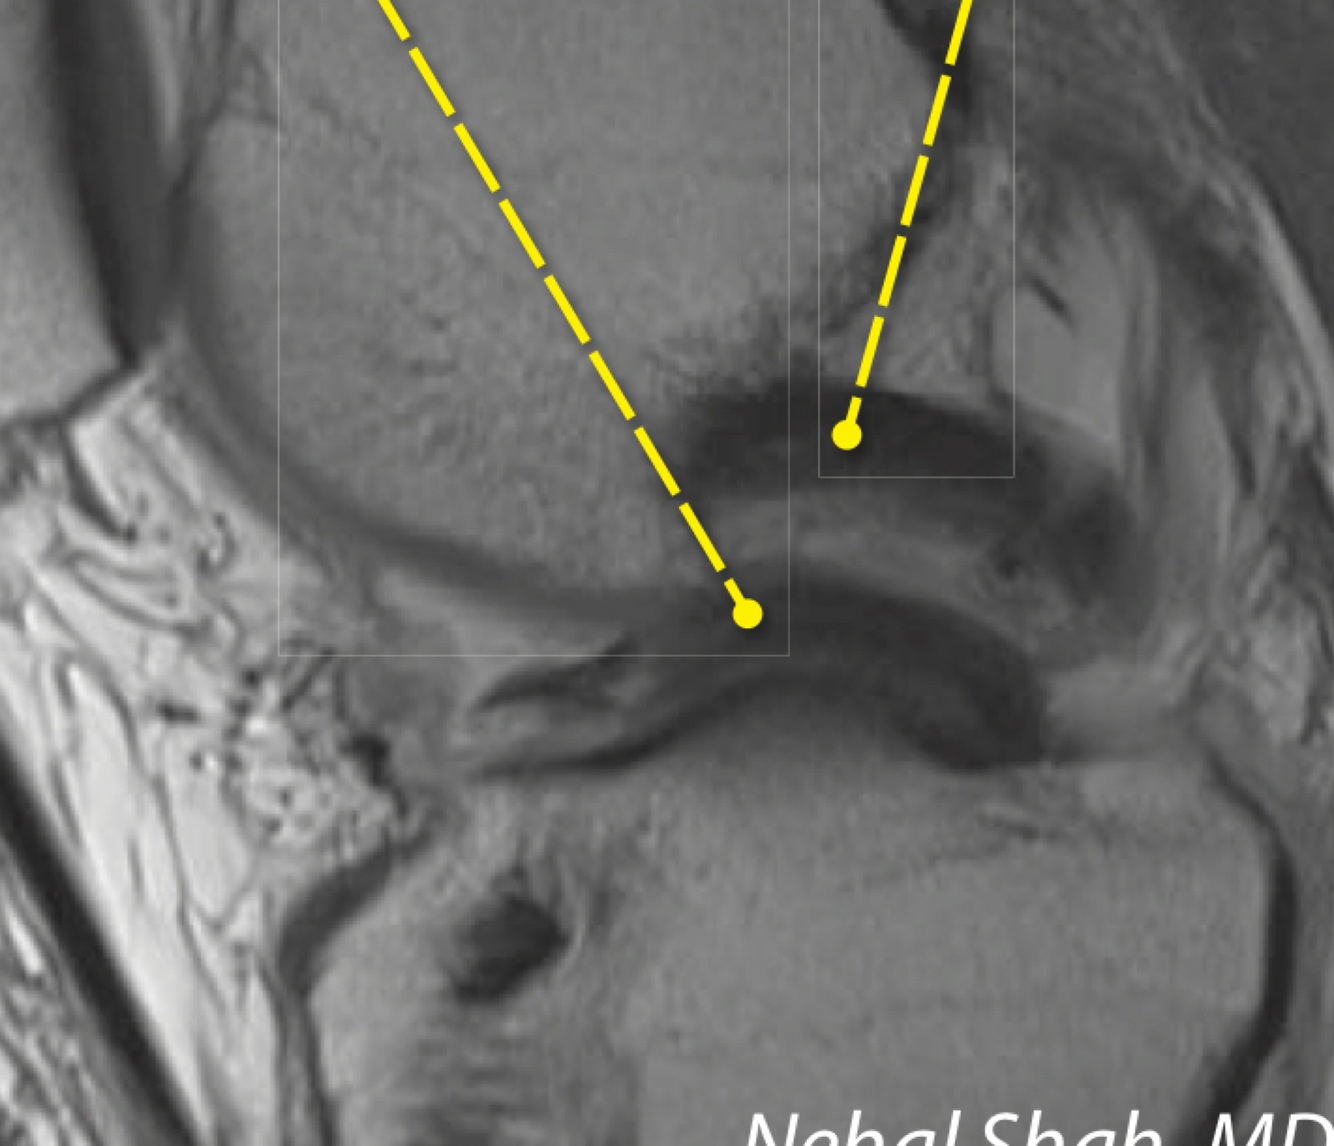

21

Q

What is this lesion called

A

Pellegrini-stieda lesion - post-traumaic calcification medial to the medial femoral condyle, which may be secondary to MCL avulsion injury

How well did you know this?